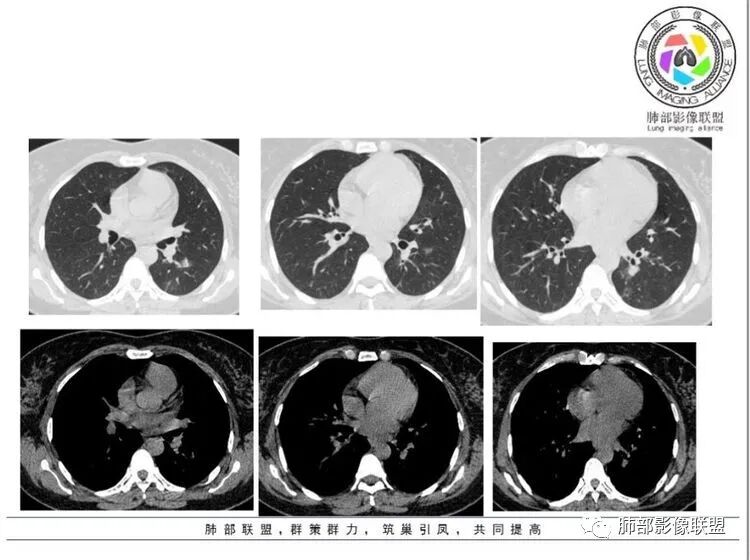

左肺散在多发斑片状影,下叶为著,左肺下叶较大团片影边缘模糊有磨玻璃影,有空泡,血管进入,气管分支似有闭塞,胸膜牵拉,抗炎治疗效果差,Tspot阳性,余隐球菌和结核目前实验室检查阴性,家属有肺结核病史,影像不是典型的结核,37岁,先考虑炎性,结核重点排查,粘液痰,需排除粘液腺癌可能,常规治疗后复查。

左肺下叶可见结节影,病灶内见坏死、钙化,边缘可见索条影,内有空洞,洞壁光滑,周边及远端肺叶可见散在结节影,考虑结核可能,鉴别腺癌

左肺结节,实变及磨玻璃影,首先考虑感染性,隐球菌?结核?

青年女性,左肺下叶团片影,边缘平直为主局部膨隆,内壁光滑小空洞,支气管穿行略扩张,血管增粗。考虑炎性肉芽肿,隐球可能大,鉴别淋巴瘤

女患 37岁 年轻 抗炎治疗病灶无好转,病灶特点左肺下叶外基底段为主胸膜下沿支气管分布病灶,病灶整体平直收缩为主,支气管未见截断,有支气管爬行特点,病灶周边散在GGO,大部分模糊,结核感染T细胞检测阳性 有肺结核密切接触史 首先考虑继发性肺结核    支气管镜灌洗液检查没有找到病原学或者肿瘤细胞证据,肺结核依据不足,建议穿刺活检,除外腺癌可能

女,37岁,慢性咳嗽2月余,治疗未见吸收,左肺下叶见实性结节及磨玻璃灶,部分边界平直,膨隆,有长毛刺,边缘稍模糊,内见空洞,内壁光整,远侧见低密度影,邻近支气管未见明显堵塞,邻近斜裂胸膜牵拉,考虑肉芽肿病变,丈夫有肺结核史,结核可能,鉴别腺癌,建议前片对比与增强及必要时穿刺活检。另左肺上叶胸膜下似见磨玻璃灶,结核?

左肺下叶实性结节,周围可见GGO,部分边缘平直并可见毛刺,内可见小空洞,壁光整,临近胸膜有牵拉,部分支气管扩张,部分层面欠通畅。考虑炎性病变可能

长短毛刺,收缩明显,小空洞,胸膜牵拉,周围略模糊GGO,支气管扩张,部分层面欠通畅。多考虑炎性病变,腺癌待排。

左肺下叶多发磨玻璃及实变影,实性病灶边缘收缩,似有微钙化及坏死,局部毛糙,牵拉胸膜,内可见空泡,空泡壁光滑,边缘可见欠清的磨玻璃影,临床咳嗽咳痰两个月,考虑炎性病变:结核可能性大。

2.左肺下叶胸膜下团片影及多发小片影,团片影长轴与胸膜平行,周围有模糊的晕,局部平直收缩,支气管近端堵塞,病灶内可见小空洞,空洞内壁光整,邻近胸膜牵拉。

结合肿块周围有多发小片、结节影等类似形态的卫星灶,病灶像炎性,没有游走性,但长时间段抗炎治疗无效,应当想到特殊感染的可能,如隐球菌感染或其他慢性炎症,如结核等。

3.患者丈夫有肺结核病史,理应考虑肺结核可能性,但患者病灶周围没有典型树芽,而且病灶的形态较为单一,分布特点都不大符合典型的结核影像学特点。